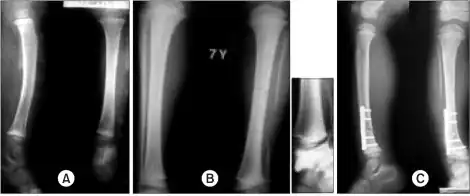

a)Radiographs show a large segmental fibular defect by chronic osteomyelitis b,c) four years later, serial radiographs show a valgus deformity of ankle due to upward migration of distal fibula -